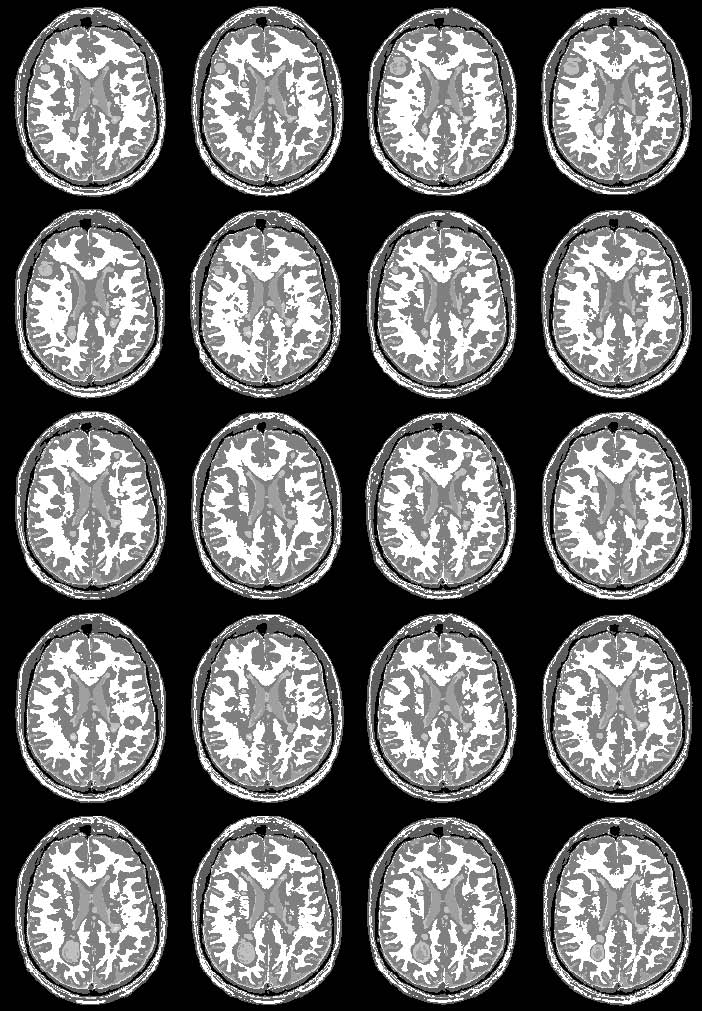

#[[media:seven.jpg|longituidinal MS, one subect, segmentaiton result without EM]]

#[[media:eight.jpg|" " " with EM]]

images:

7. longituidinal MS, one subect, segmentaiton result without EM

8. " " " with EM